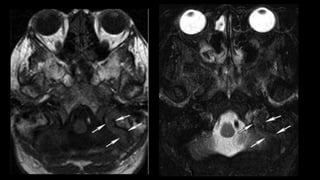

Affects cortex in NONVASCULAR distribution

ABSCESS SHOWING DIFFUSION RESTRICTION

• #58 Right occipital pyogenic abscess showing marked diffusion restriction within the core on DWI and ADC maps and a peripheral enhancing pattern on T1 post gadolinium